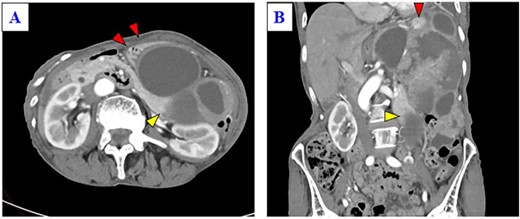

A 79-year-old woman was referred to our hospital because of nausea for about 3 months. Her medical and family histories were unremarkable. On admission, her vital parameters were as follows: temperature, 36.6°C; blood pressure, 120/84 mmHg; heart rate, 72 beats per minute (regular); respiratory rate, 15 breaths per minute and oxygen saturation, 99% on room air. Physical examination revealed a soft mass was palpable in the left upper quadrant. Laboratory investigation revealed slight anemia (hemoglobin: 10.3 g/dL), but other results, including the serum tumor markers carcinoembryonic antigen, cancer antigen 19-9 and cancer antigen 125, were within normal ranges. Abdominal computed tomography (CT) revealed a large tumor with multilocular cystic and solid components, and only a small amount of normal splenic parenchyma remained. And the tumor extensively compressed the stomach ventrally. The boundary between the pancreatic tail and the hilum of the spleen was somewhat unclear, but no obvious mass lesion was observed in the pancreas (Fig. 1A and B). On magnetic resonance imaging, the solid part included an uneven high signal on T1-weighted images and a low signal on T2-weighted images, suggesting internal bleeding (Fig. 2A and B). On a positron emission tomography scan, 35.9 points of 18F-fluorodeoxyglucose accumulation of standardized uptake value showed in the only solid part of the tumor (Fig. 3). Although a definitive preoperative diagnosis could not be made, angiosarcoma originating in the spleen was suspected first, and laparotomy was performed.

(A) Enhanced CT shows a huge mass lesion with a mixture of cystic and solid parts, occupying the left upper quadrant and flank, and the tumor expansively compressed the stomach ventrally (red arrows). (B) Only a small portion of the normal spleen parenchyma remains (red arrow). The tail of the pancreas is partially in contact with the tumor (yellow arrow), but the border of the pancreas is relatively smooth.